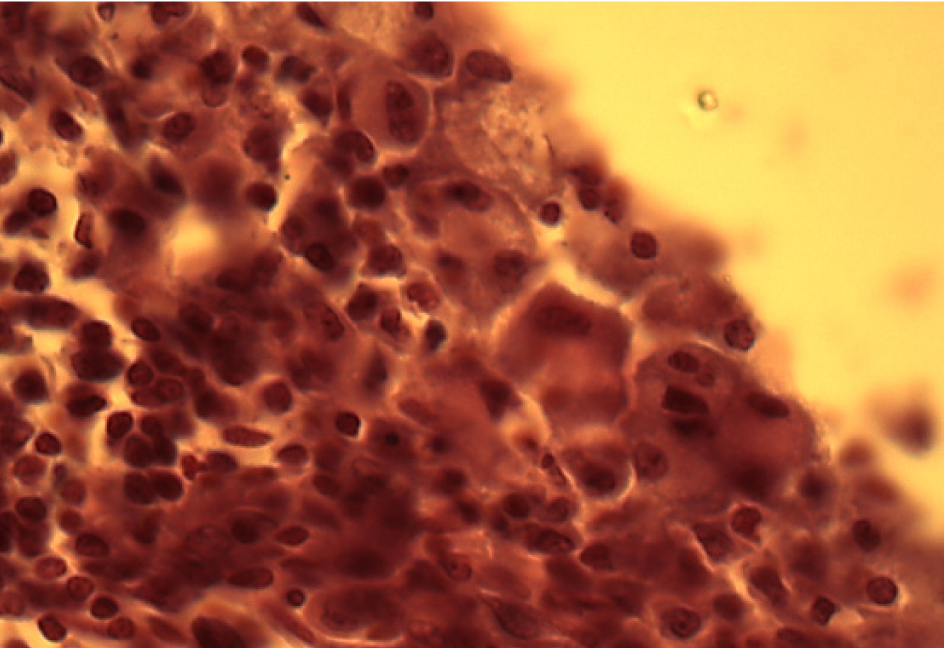

В интерстициальной ткани выявляются скопления многоядерных макрофагов с фагоцитированными частицами фталата свинца, что указывает на выраженную макрофагальную реакцию (рис. 2).

Рис. 2. Скопление крупных многоядерных макрофагов. Окраска гематоксилином и эозином. Ок. 10. Об. 100. Иммерсия